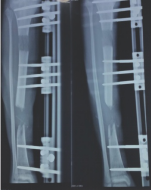

External Fixator is a device uses for stabilization and immobilization of long bone open fractures. LRS is an external fixator used for treatment of bone defect ,non-union and shortening of bone. It consists of a long rod and clamps which is connected to bone by means of schanz pins. It is available in various of sizes. It can be applied in both adults and paediatrics.

1. LRS application in a bone gap. Here bone is transported from above down wards

2. LRS application in a large bone defect. Here bone is transported from either side of bone

3. LRS application in a very small defect. Here bone compressed on one side and lengthened on another end

4. LRS application in a shortening. Here bone is lengthened

5. LRS application in a shortening .Here bone is lengthened on either side.

So LRS can be used in various indication like ilizarov. But it is less stable than ilizarov as it is stable in one plane